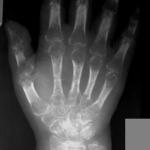

Sudeck’s Atrophy (Reflex Sympathetic Dystrophy Syndrome)

Diagnosis: Sudeck's Atrophy (Reflex Sympathetic Dystrophy Syndrome)

Findings: Adult female presented for follow-up of...